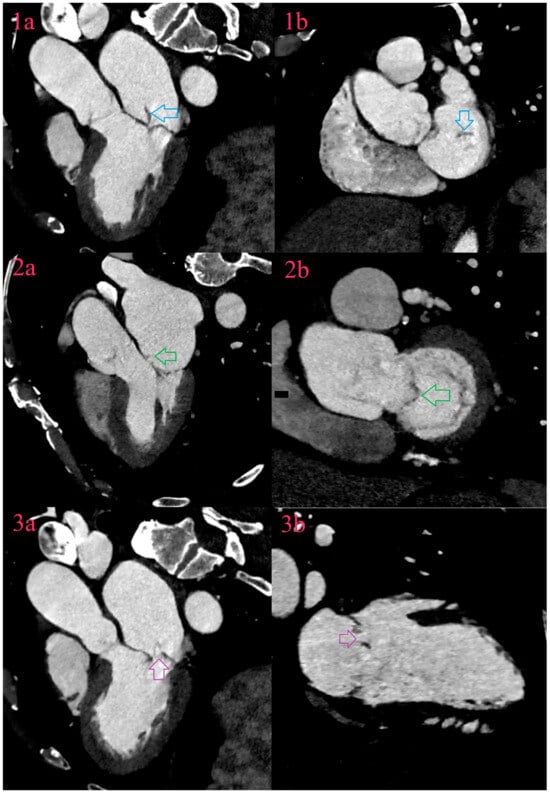

6.1. Vegetations

6.2. Aneurysms

6.3. Perforations